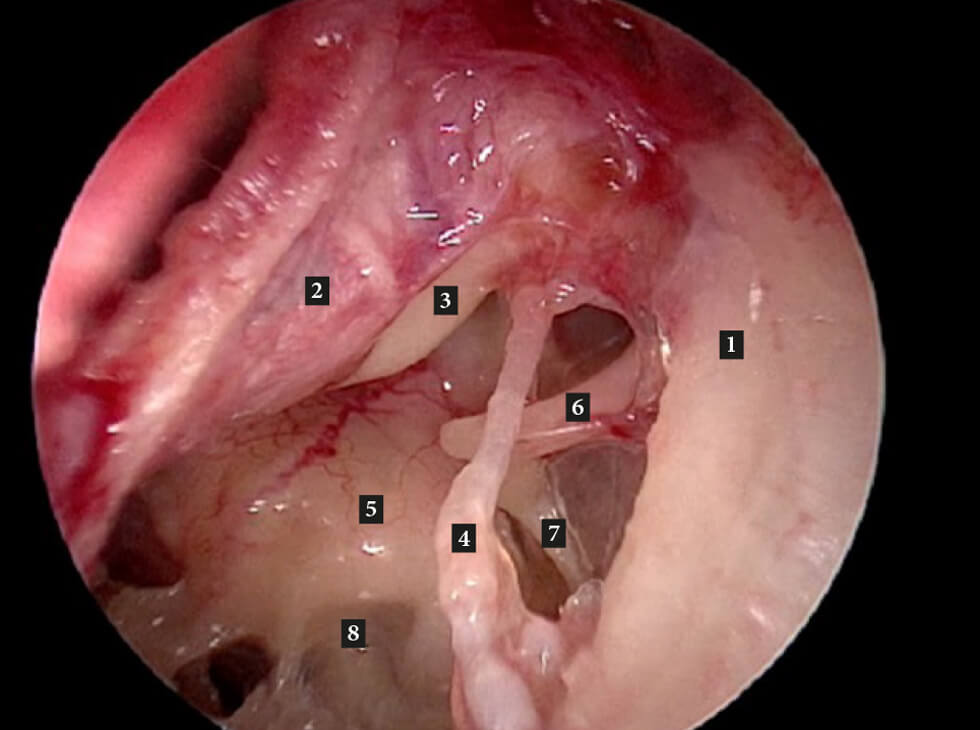

Figure A: Left middle ear. 1. Outer attic wall; 2. Tympanomeatal flap (reflected forwards); 3. Handle of malleus;

4. Chorda tympani; 5. Promontory; 6. Long process of incus; 7. Stapedius tendon.